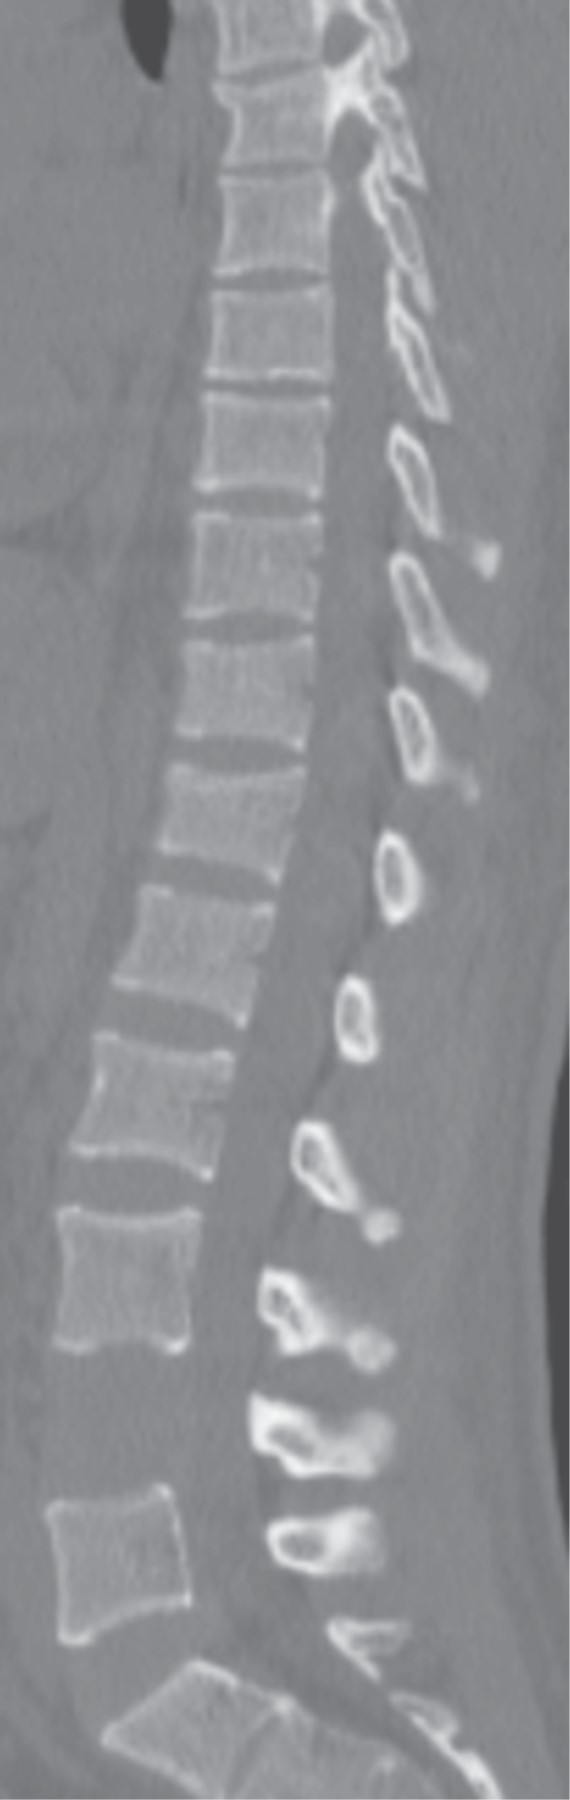

El examen radiográfico demostró rectificación de la columna cervical, además en radiografía lateral de columna lumbar se observó disminución de la plataforma superior del cuerpo vertebral de L4, con afectación de columna anterior y media de Francis Dennis, sin retropulsión a conducto medular, también en radiografía anteroposterior (AP) de columna lumbar se advirtió una incongruencia a nivel de L4 con ausencia de fusión de cuerpos vertebrales con diástasis de ocho milímetros (Figura 2).

Se realizó tomografía de columna lumbar en cortes sagital, coronal y axial, así como reconstrucción en 3D, donde se identificaron lesiones en alas de mariposa y también se reconoció afectación en cuerpos vertebrales de T5-T6 y T12 (Figuras 3, 4, 5 y 6).